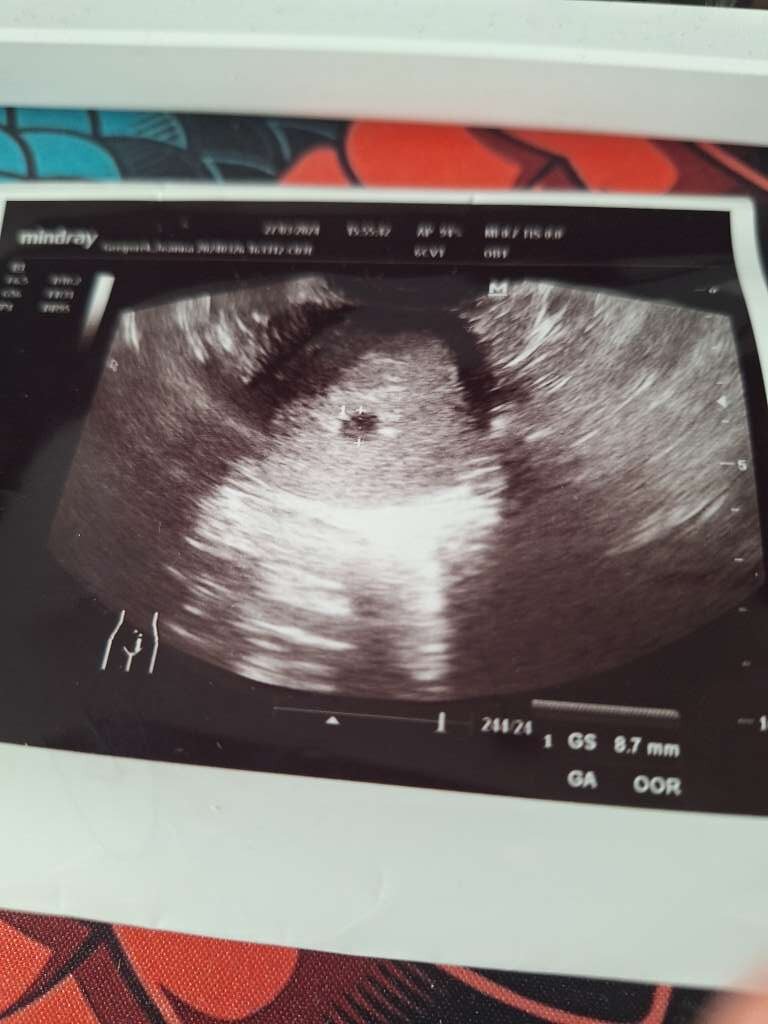

Byłam na USG jest zarodek z akacją serca, ale co z tego jak wychodzi 5+5 a ja jestem już 7+4 i nawet lekarka kręciła nosem że coś nie tak, dodatkowo pęcherzyk żółtkowy ma średnicę 7mm a powinien max 6 i to też źle wróży o wadach genetycznych. Jak znowu będę musiała to przeżywać to się załamię. Jak ta ciąża będzie się rozwijać to napewno robię amniopunkcję w 15 tc